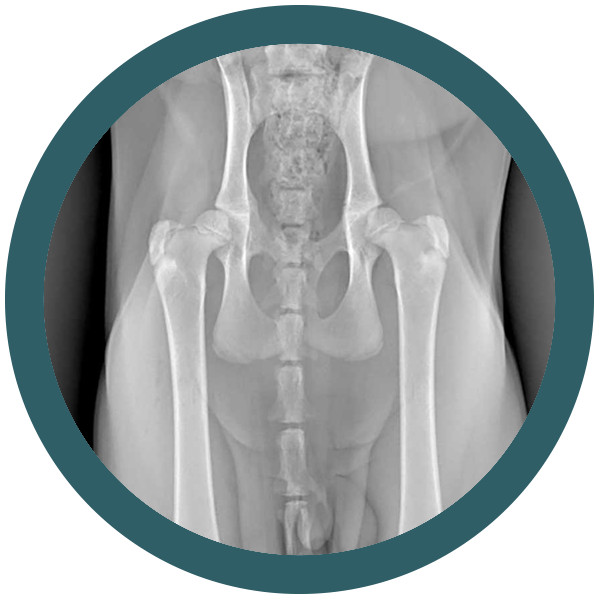

Come riconoscere una displasia dell’anca nel gatto

Osteocondrodisplasia Scottish Fold: quando la dolcezza delle orecchie nasconde un problema serio